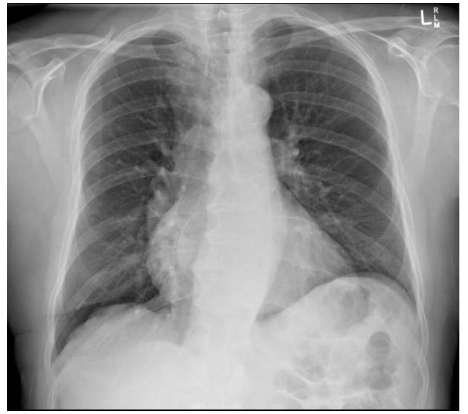

Qual das seguintes patologias abaixo estaria mais relacionada aos achados da seguinte radiografia de tórax?

Qual é a artéria assinalada na seguinte figura, considerando essa incidência oblíqua anterior esquerda?